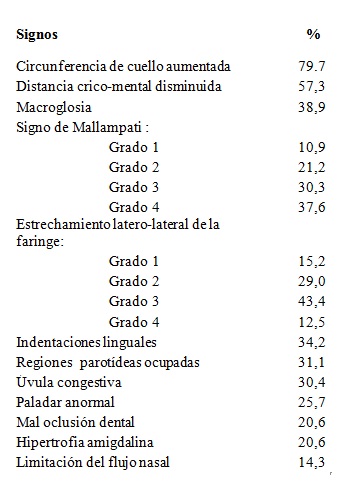

Los signos frecuentes se presentan en la Tabla 6. La figura 3, La figura 4, La figura 5 y La figura 6 describen los hallazgos de importancia en el examen de cuello y de la orofaringe, que habitualmente son escasamente destacados en la enseñanza de la semiología. La circunferencia de cuello fue de 45,9 ± 3,9cm en hombres (normal hasta 42) y 41,8 ± 3,7cm en mujeres (normal hasta 38). El espacio crico-mental se evaluó cualitativamente15. En el examen de la orofaringe, se evaluaron los grados de Mallampati16, como predictores de severidad de apneas del sueño. Los grados más altos se asociaron a IAH mayores, aunque en forma no significativa (Figura 7).

Tabla 6: Examen físico.

Tabla 6. Frecuencia de signos físicos en el grupo de pacientes con historia clínica electrónica (n=447).